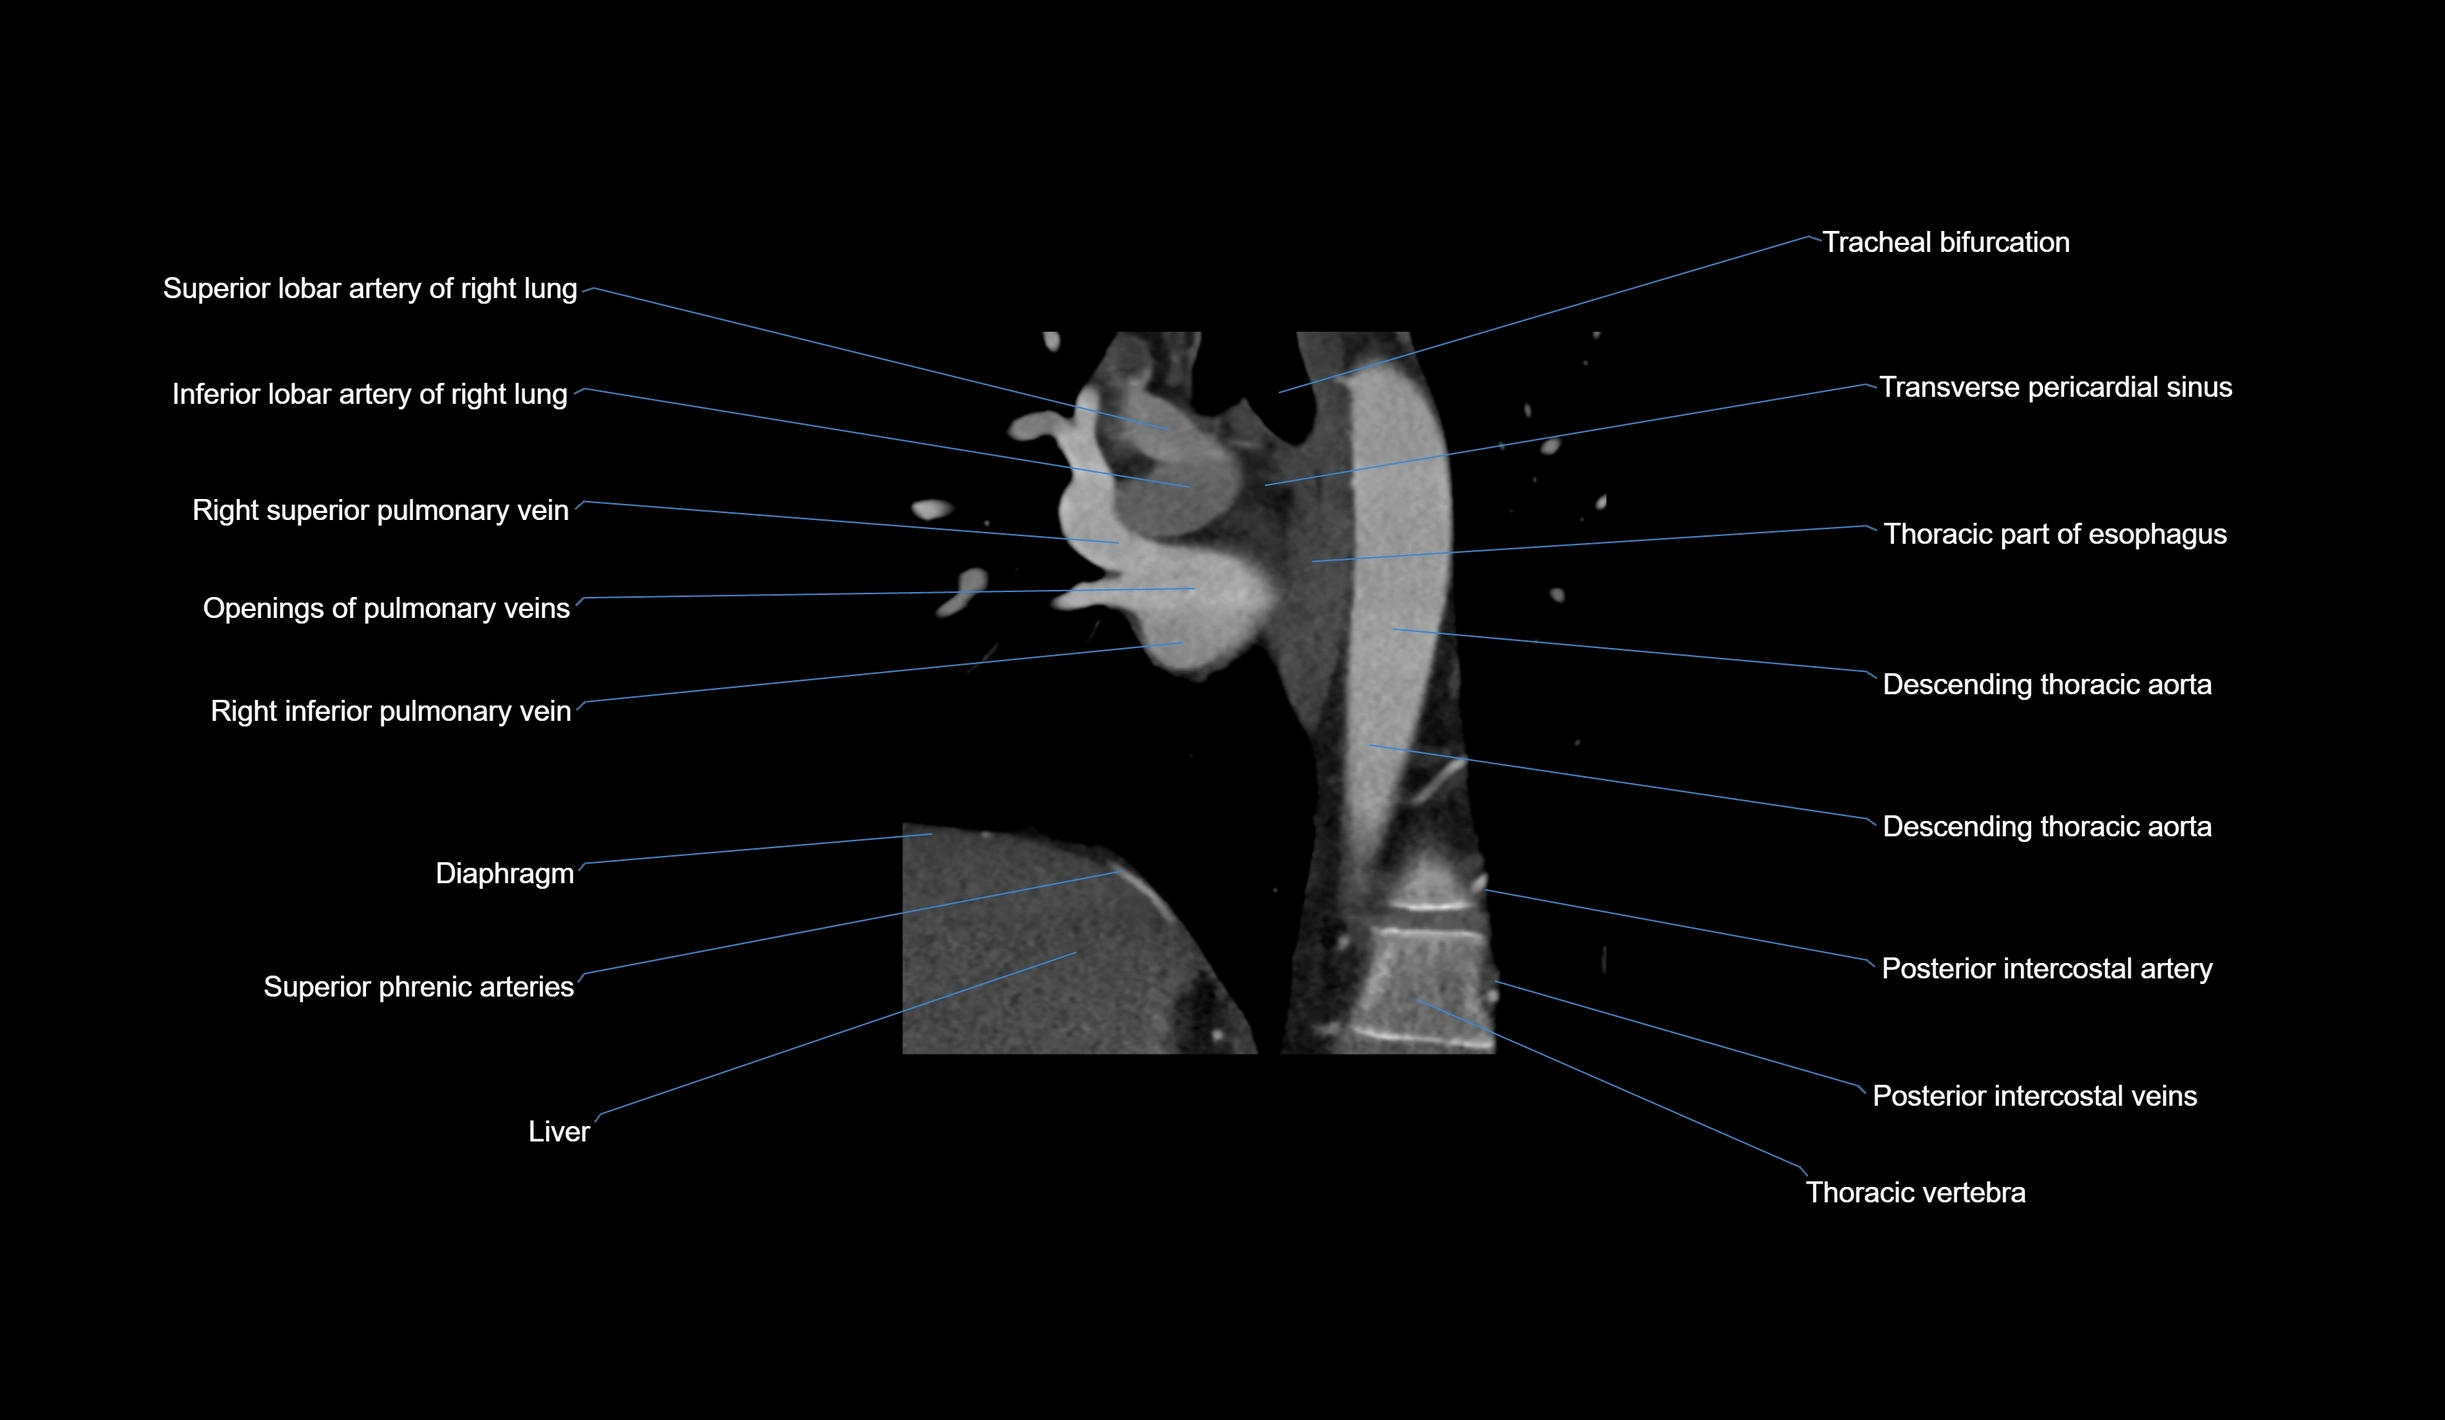

- Superior lobar artery of right lung

- Inferior lobar artery of right lung

- Right superior pulmonary vein

- Openings of pulmonary veins

- Right inferior pulmonary vein

- Diaphragm

- Tracheal bifurcation

- Transverse pericardial sinus

- Descending thoracic aorta

- Posterior intercostal arteries

- Posterior intercostal veins

- Carina of trachea